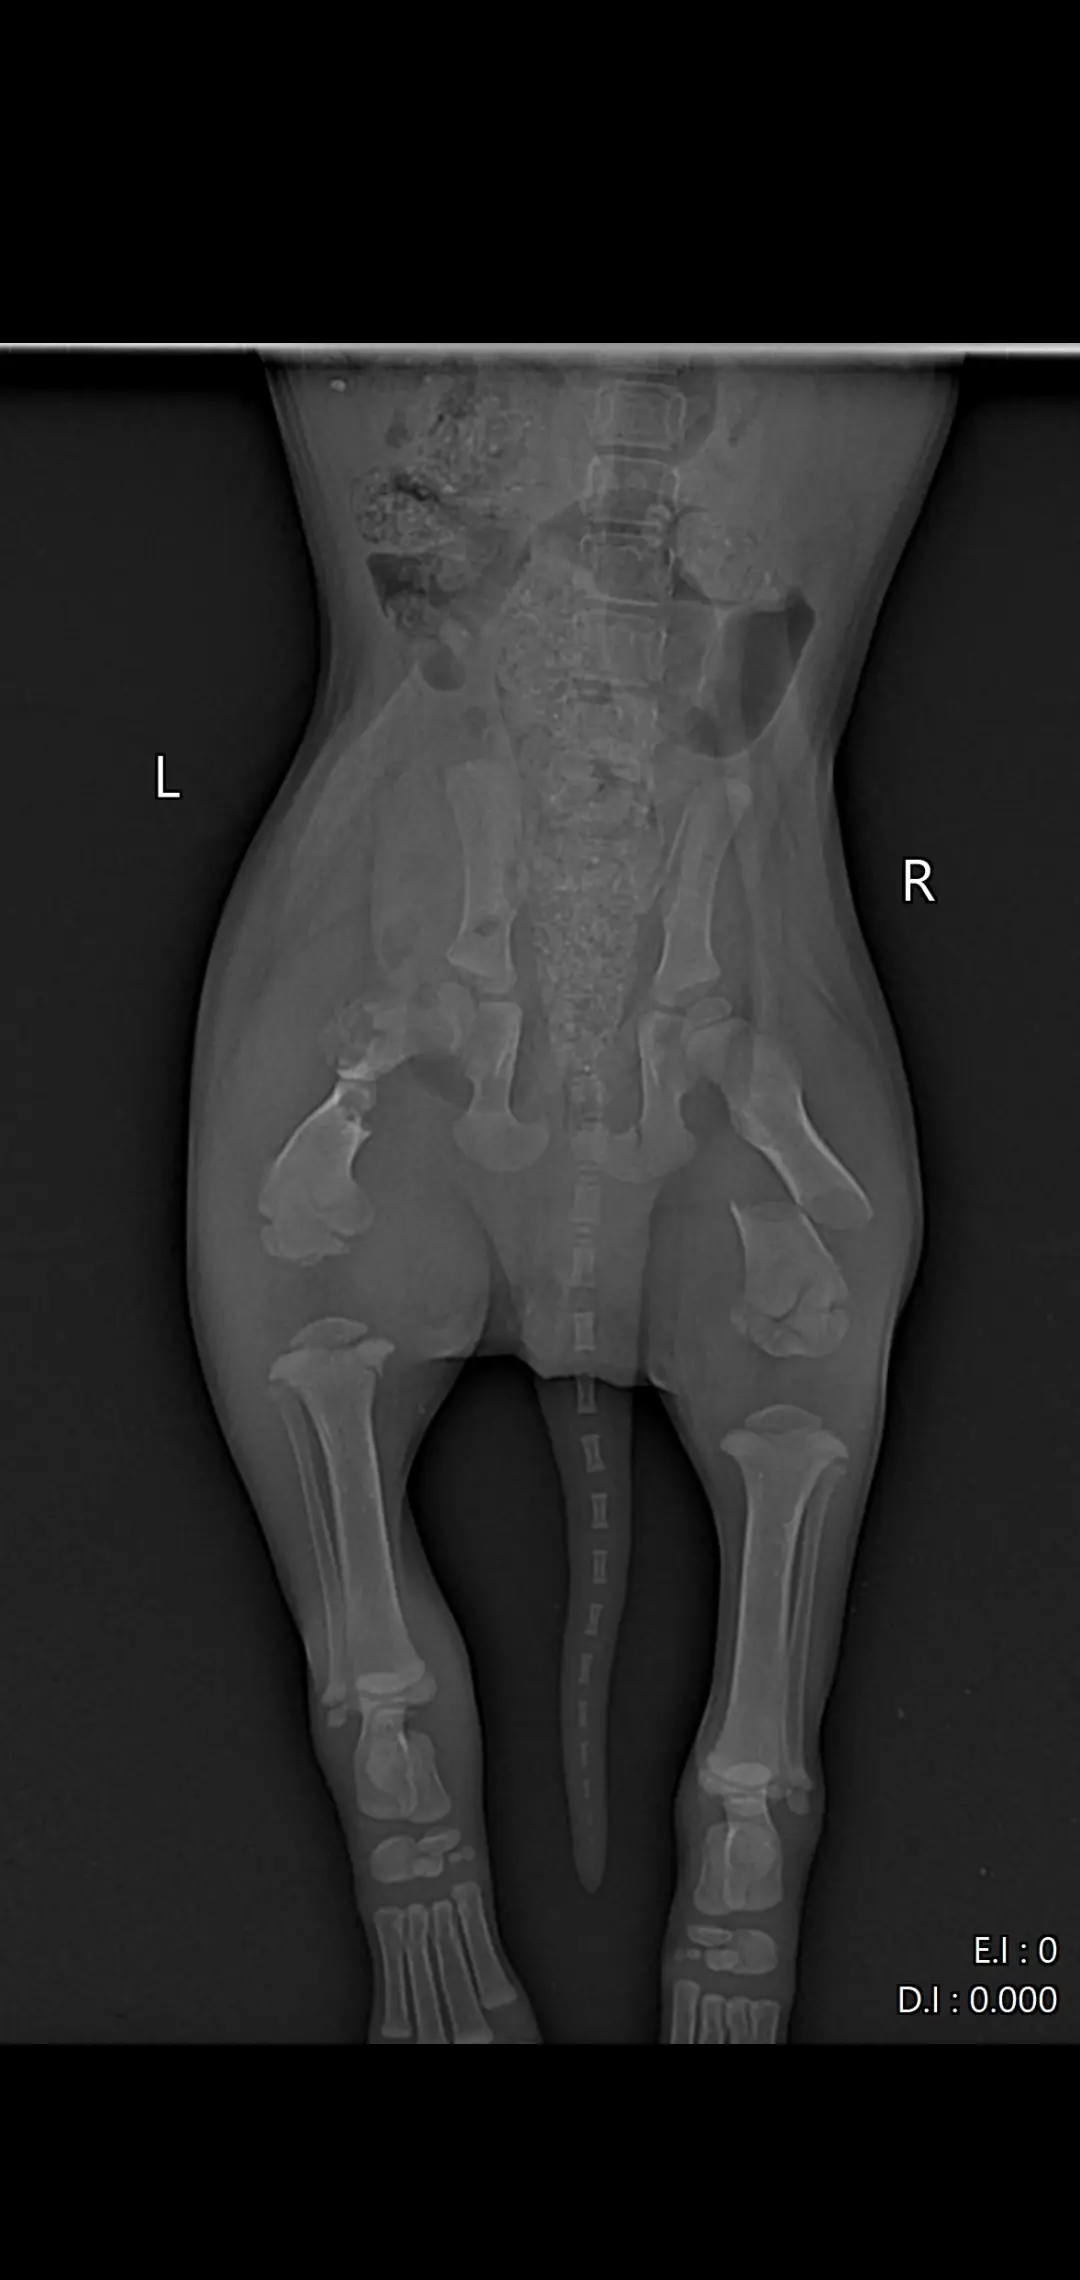

Намерих го в тежко състояние – със счупен таз и две счупени крачета. Не може да се движи, плаче при всяко докосване, но въпреки всичко се бори  да живее. 🐶😭

Бях с него във ветеринарна клиника „Провет“ в Пловдив (Тракия). Лекарят др Ташев го прегледа,оператор д-р Пачев (младши) ми каза, че има шанс да живее, но е нужна спешна операция и за двете крачета, която струва 1200 евро 😔

📸 Прилагам снимки от рентгена, за да видите колко тежко е състоянието му…плюс какво му беше изписано и направено в клиниката